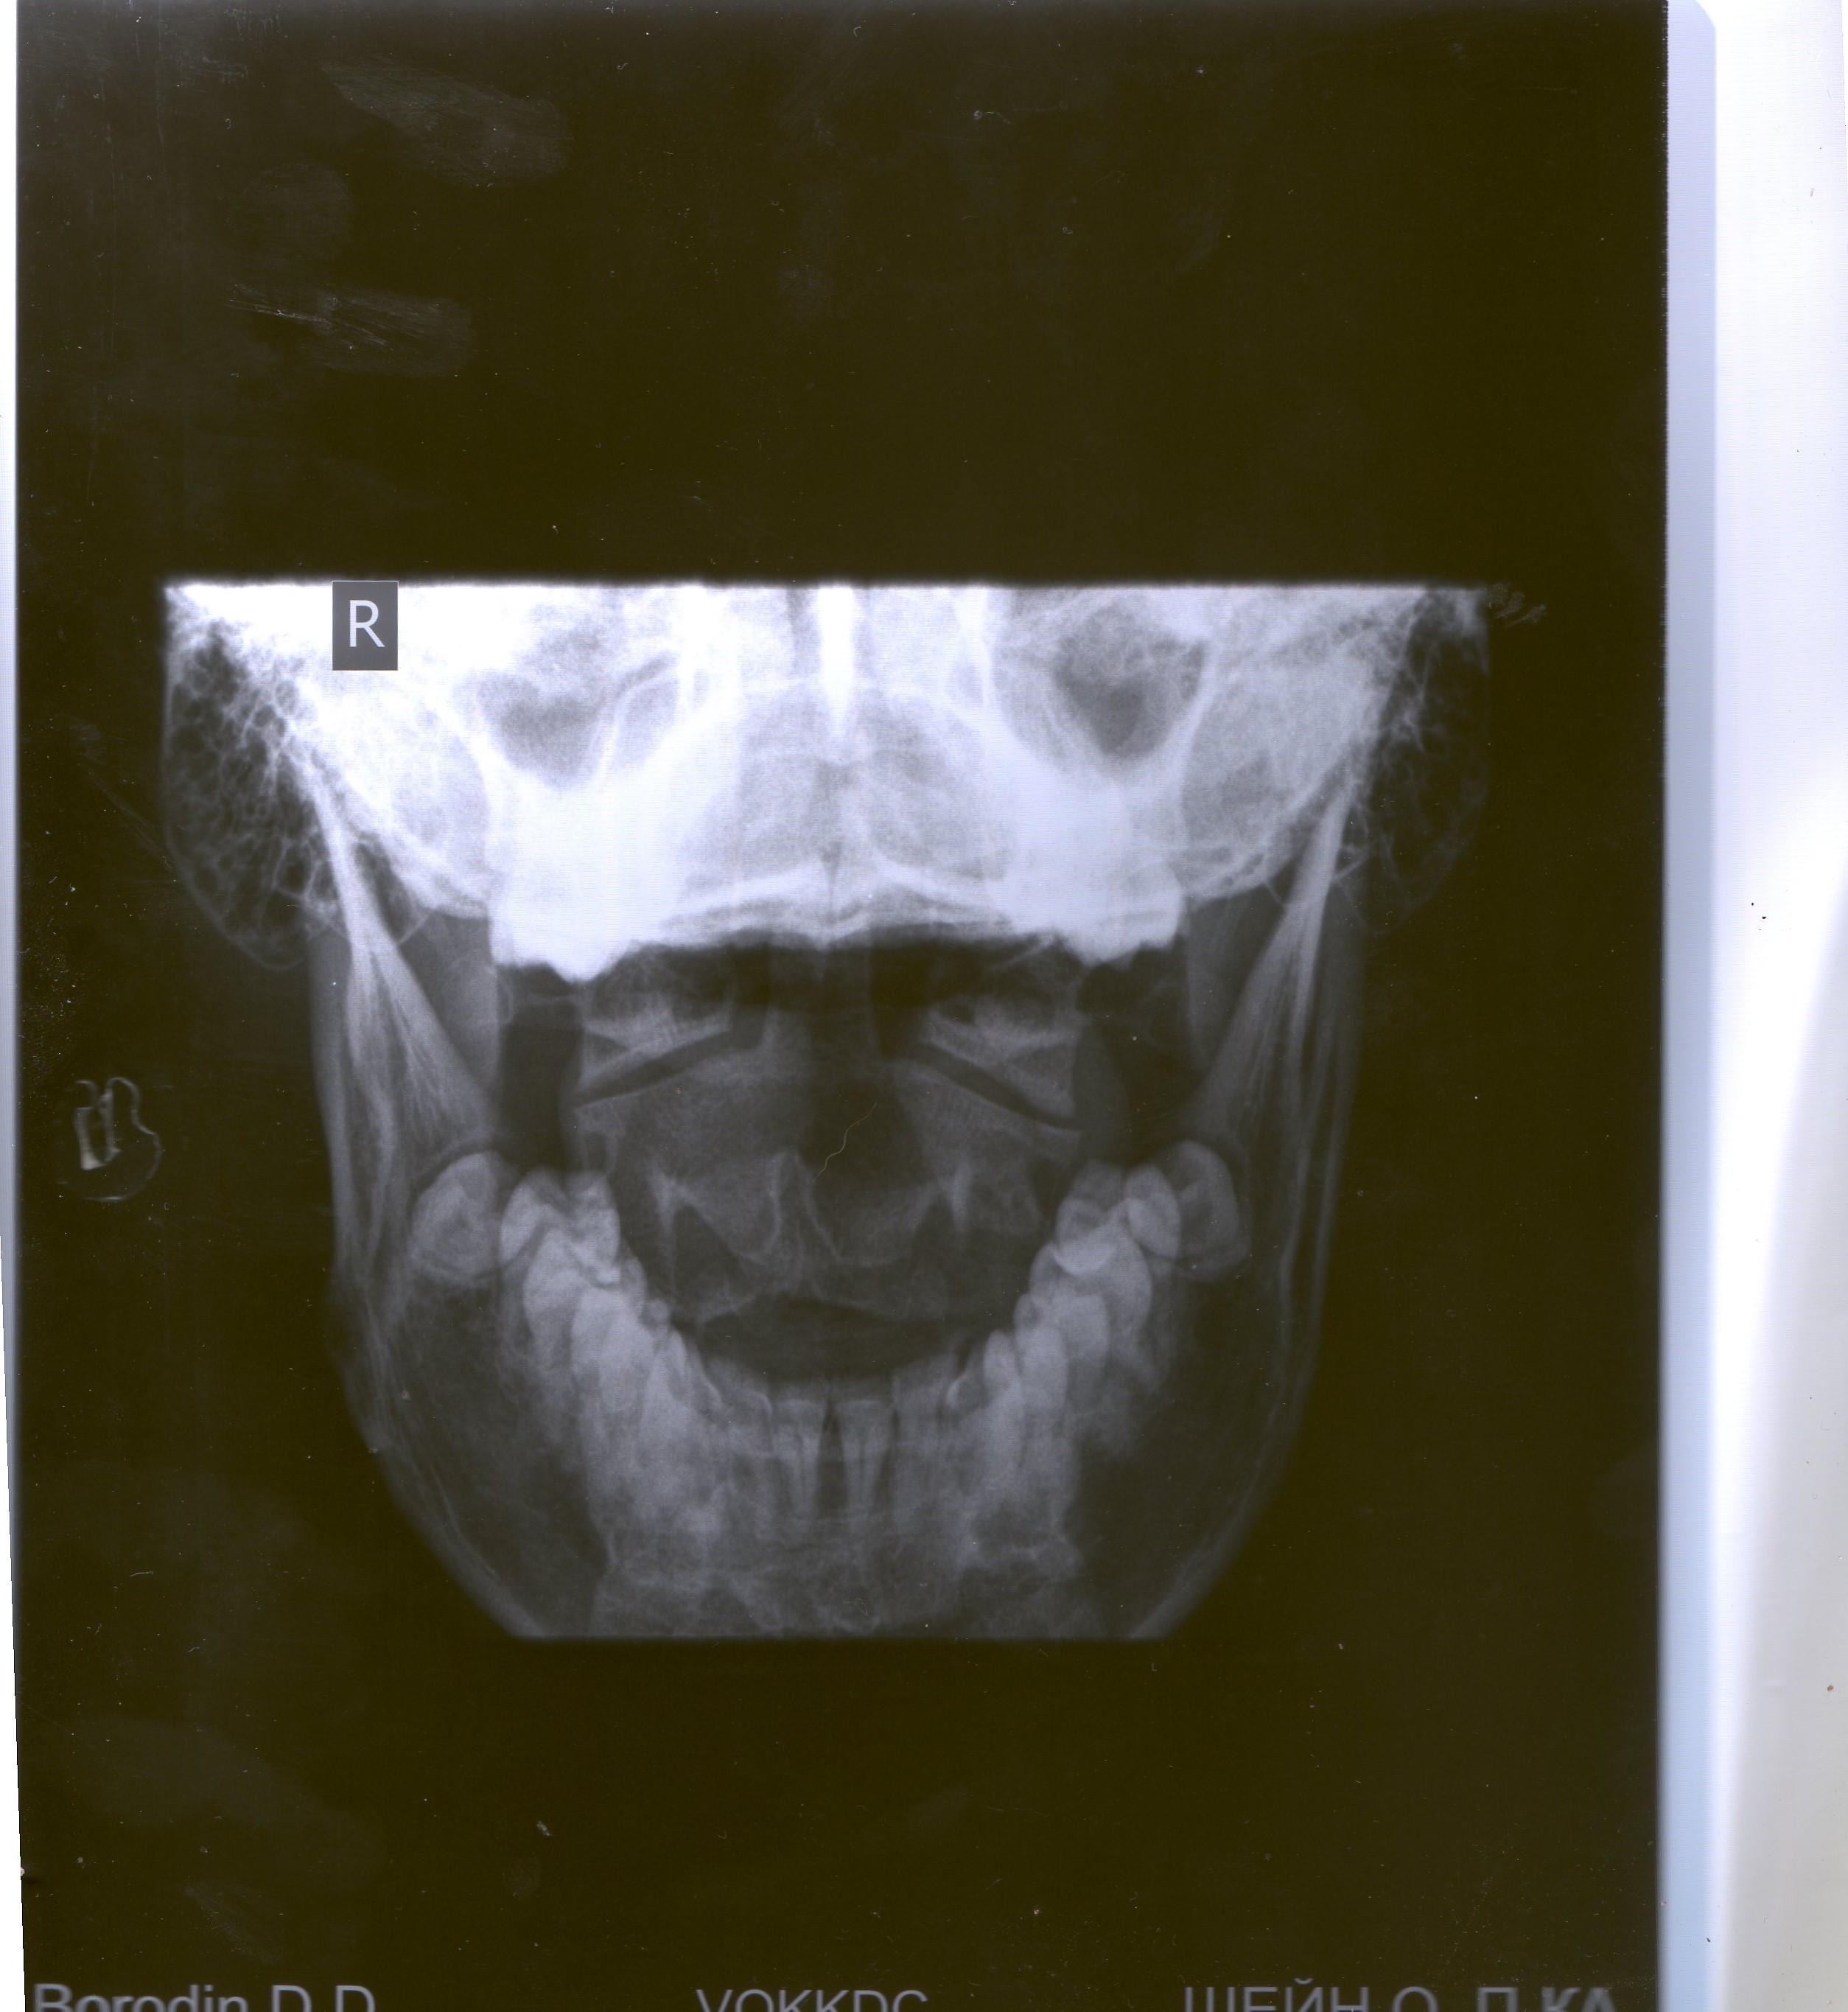

Здравствуйте !Мне 23 года ,началось всё после тренажерного зала ,3 года назад ,пол года назад стало ещё хуже при наклонах вниз ,резко что то в голову ударило ко будто появились мушки в глазах ,мерцание яркого света ,давление стало 130 на 85 и до 160 на 100,раньше было 120 на 70,тахикардия ,головокружения ,пошатывания ,и т.д Ставят синдром позвоночной артерии ,хирург из Литвы говорит что дело в лестничных мышцах и их надо удалить .Но мои сомнения берут в верх , я думаю что компрессия где то в костном канале .Может ли это быть нерв в с 2 ?Или вчг ?Гидрацифалия с детства у меня такая ,компинсированная ,что написали выреженная это не так .Пожалуйста ,подскажите ,что мне делать ?Высылаю Вам обследования мр-ангиограмма артерий шеи https://yadi.sk/d/ZZRccXTycAwYs ,мрт головы ,шеи,грудного отдела ,поясницы

https://yadi.sk/d/6sLfPlEocAw4V ,ссылка на снимки ,рентген,уздг,ТКДГ https://yadi.sk/d/NooJd2FecGSAM с Уважением Дмитрий !